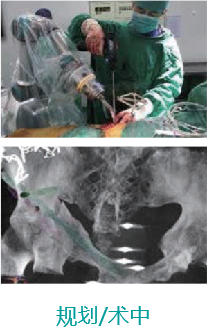

天玑II 辅助骨盆髋臼骨折内牢靠术

机械人辅助优势:天玑II机械臂最后控制快速选择和执行手术妄想,,,,,,,,通道螺钉精准定位,,,,,,,,镌汰术中透视。。。。。。。

病例泉源:北京积水潭医院